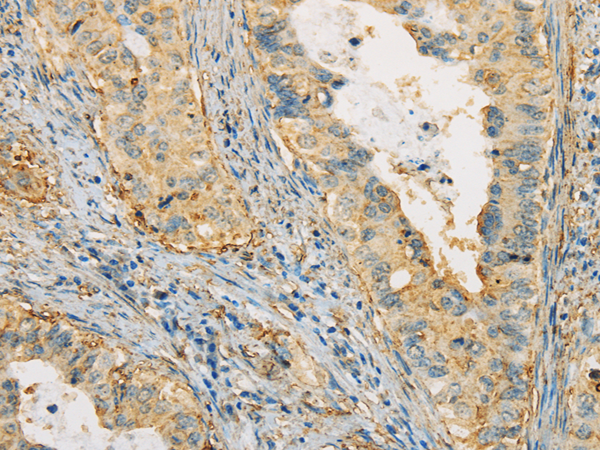

IHC positive control: |

Human ovarian cancer and human cervical cancer |

IHC Recommend dilution: |

25-100 |